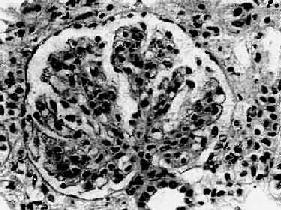

| 四、弥漫性膜性增生性肾小球肾炎弥漫性膜性增生性肾小球肾炎(diffuse membranoproliferative glomerulonephritis)又称系膜毛细血管性肾小球肾炎(mesangiocapillary glomerulonephritis),其病变特点为弥漫性肾小球毛细血管壁增厚和系膜增生。各种年龄都可发病,但多见于青年和中年人。起病缓慢,是一种慢性进行性疾病。早期症状不明显,临床症状表现不一,常有血尿、蛋白尿。约半数起病时即表现为肾病综合征,并常有高血压和肾功能不全。有些病人的血清补体降低,故又称为低补体血症性肾小球肾炎(hypocomplementemic glomerulonephritis)。 【病理变化】 肾小球系膜细胞和基质增生。系膜区增宽,其间常有数量不等的中性粒细胞浸润。增生的系膜组织逐渐向周围毛细血管伸展,侵入毛细血管基底膜与内皮细胞之间,使毛细血管壁增厚,管腔狭窄(图12-13)。应用银染法可见增厚的毛细血管壁呈车轨状或分层状。由于系膜增生,系膜区增宽,使毛细血管丛呈分叶状。严重时可使轴心处呈结节状。病变继续发展,增生的系膜组织可环绕全部毛细血管壁,使管壁显著增厚,管腔狭小甚至阻塞。有时部分肾小球内可有新月体形成。晚期,系膜及肾小球纤维化、硬化,整个肾小球形成无结构的玻璃样小团。相应的肾小管萎缩,间质纤维组织增生,有多数淋巴细胞及单核细胞浸润。

图12-13 膜性增生性肾小球肾炎 肾小球系膜细胞增多,增生的系膜组织侵犯毛细血管,毛细血管壁增厚,腔狭小,肾小球丛呈分叶状 电镜观察可见肾小球系膜增生,毛细血管基底膜不规则增厚。增生的系膜组织沿毛细血管基底膜和内皮细胞之间向毛细血管周围部分伸展,甚至环绕全部毛细血管壁,使毛细血管壁增厚。肾小球内有大量电子致密物沉积。根据沉积物的部位,可将膜性增生性肾小球肾炎分为3型: Ⅰ型电子致密物沉积在肾小球基底膜内侧,内皮细胞下,大小不等,常聚积成大团块状(图12-14,图12-15)。系膜内和上皮细胞下偶然也可见有少量小而不规则的沉积物。